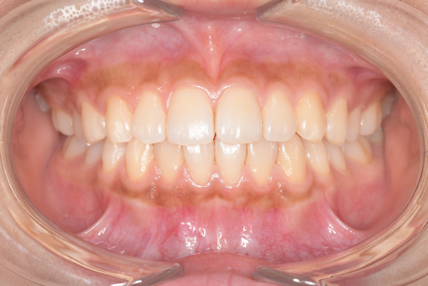

クリーニングの症例

現在の治療費と異なる場合がございます。最新の治療費は料金表をご確認ください。CASE 1

Before

After

基本情報

| 主訴 | 見た目をきれいにしたい |

|---|---|

| 治療期間 | 6ヶ月 |

| 治療費 | ジルコニアボンド(セラミックの被せもの)¥165,000×7(税込み) オフィスホワイトニング4回 ¥4,400×4(税込み) ホームホワイトニング¥11,000 |

| リスク・副作用 | かみ合わせがとても強い方の場合、稀に割れてしまうことがあります。 |

| 先生からの提案 | 上の前歯6本と右下の2番目の歯はセラミックの被せもので治療。 残りの下の前歯5本はプラスチックの材料で虫歯を治療し、 ホワイトニングをおこないました。白くなったご自身の歯の色に合わせてセラミックの 被せものを作成しています。 模型上で完成後をシュミレーションし、上の歯茎の位置をきれいに見えるように 揃えています。(外科処置はしていません) |